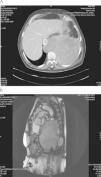

Varón de 66 años, fumador de 40 paquetes al año, con HTA, dislipemia, intolerancia a la glucosa y arteriopatía periférica con bypass iliofemoral izquierdo en 2001. Remitido a neumología por los hallazgos del TAC torácico solicitado por derrame pleural izquierdo en una radiografia de tórax. En el TAC (fig. 1A) existe una gran masa extrapulmonar diafragmática izquierda de 15,6cm. Heterogénea con zonas de calcificación periférica. Se introduce en el espacio epidural a nivel D11 y D12 con estenosis de canal. Asintomático desde el punto de vista respiratorio, sólo refería dolor en miembros inferiores sobre todo nocturno de meses de evolución. En la exploración física destacaba en la auscultación pulmonar hipoventilación en base pulmonar izquierda hasta campo medio. La analítica básica fue normal y tenía ecocardiograma con hipertensión pulmonar moderada. Se realizó RMN (fig. 1B) en la que se confirman los hallazgos del TAC y se observa contacto con la aorta toracoabdominal sin infiltrarla y signos de compresión medular iniciándose tratamiento con dexametasona.